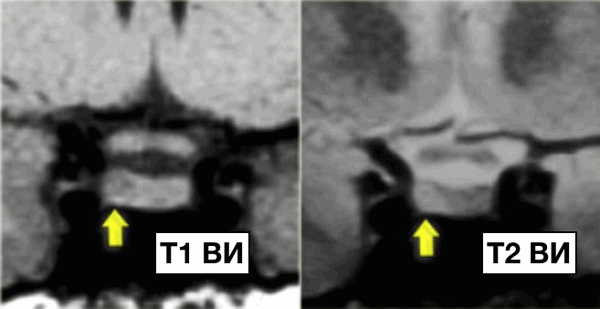

Микроаденома гипофиза

Микроаденома гипофиза - это опухоль, локализующаяся в гипофизе, размерами менее 10 мм в диаметре.

На данных изображениях представлен классический случай микроаденомы. На Т1 взвешенных изображениях в гипофизе визуализируется опухоль 3-4 мм в диаметре, незначительно гипоинтенсивнее по отношению к нормальной ткани гипофиза, а на Т2 взвешенных изображениях незначительное гиперинтенсивное.

Следовательно, дифференциальный диагноз выглядит следующим образом:

- микроаденома гипофиза

- киста карма Ратке

NB! Данные две патологии не всегда возможно отдифференцировать друг от друга.

Безконтрастная МРТ в диагностике микроаденом гипофиза имеет чувствительность в 70%. Контрастирование не всегда необходимо, даже если на нативных изображениях патология не выявлена так, как пациентам проводят схожее симптоматическое лечение, как и пациентам с выявленной микроаденомой (чаще это женщины с гиперпролактинемией).

Цель исследования, соответственно, поиск опухоли размерами более, чем 10 мм.

Контрастирование необходимо в случаях, когда необходимо установить точную локализацию патологического процесса для последующего оперативного вмешательства. Контрастирование обязательно при неэффективном симптоматическом лечении у пациентов с опухолью гипофиза (например, при болезни Кушинга).